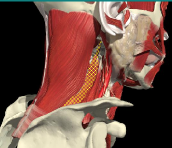

LOCALIZATION OF MUSCLES IN DEEPER LAYERS

Layer 1

Layer 2

Layer 3

Splenius Capitis

Semispinalis Capitis

Longissimus Capitus

Semispinalis Cervicis

ACCURACY OF LOCALIZATION – DEEPER LAYERS